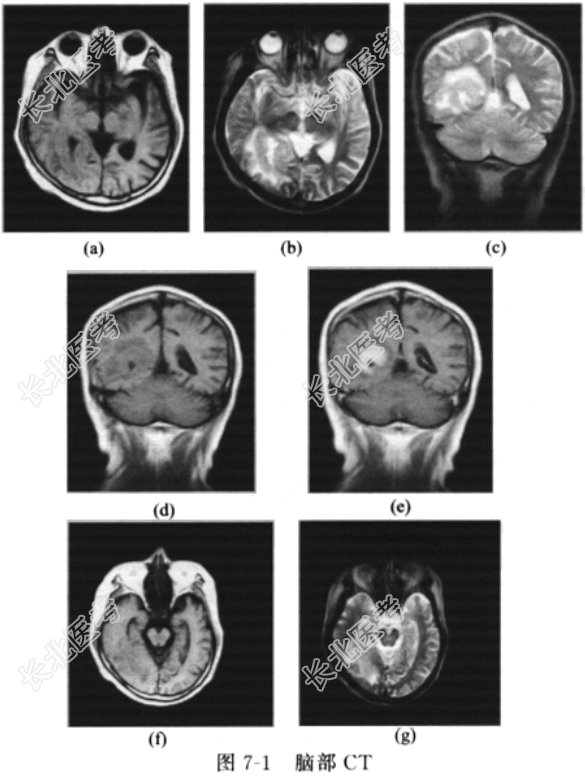

- [材料题] 患者男性,52岁,因“突发全身抽搐1次,不省人事10min”入院。入院前于急诊行CT(图7-1)示:右侧侧脑室后角周围占位性病变,脑萎缩。查体:神志清楚,口角无歪斜,伸舌居中,生理反射存在,病理征阴性。入院初步诊断:脑肿瘤?继发性癫痫。

男性患者因抽搐、不省人事入院,入院后MRI示:右侧枕叶见大小约65mm×45mm×45mm的长T1、T2异常信号影,边界模糊,边缘不规则,增强后病灶内不规则团状强化,周围水肿带,右侧侧脑室及附近脑沟未见明显受压,考虑淋巴瘤或转移瘤。血尿粪常规、胸部X线片、腹部B超、肿瘤标志物(CEA、CA19-9、CA125、CA153、CA72-4、SCC、NSE、PSA)均未见异常,考虑淋巴瘤。经手术切除病理示弥漫大B细胞淋巴瘤。